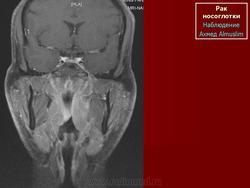

ЛОР. Онк. Рак носоглотки. +

Рак носоглотки